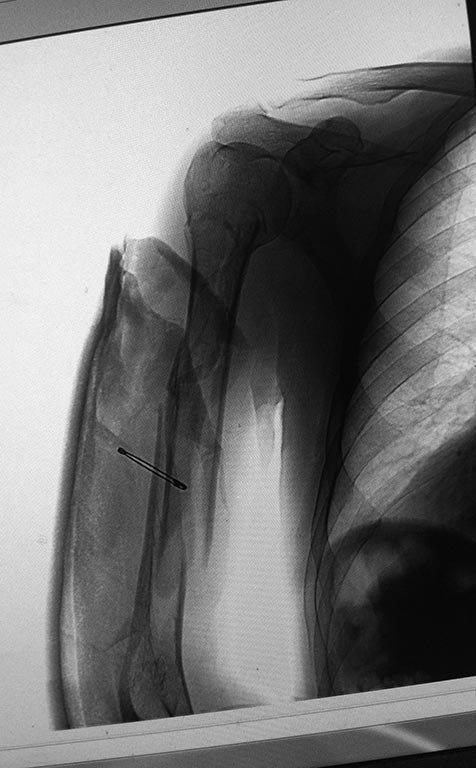

Спасибо, всем откликнувшимся!

Взвесив все, решили остановиться на функциональном методе лечения, тем более, что пациент не относится к категории high demand.

Пока наложил что-то между повязкой Колдуэлла и лонгетой по Турнеру. Иммобилизации съемная, потому что имеются приличных размеров фликтены по задней поверхности. Так же сделал Р-контроль левого плеча.

Пациент вполне комплаентный. Рекомендовал явиться через 2 недели.